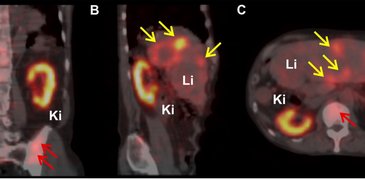

220316 Muller Fig1.jpg

17 mars 2022 A superior radionuclide for cancer treatment

Radioactive isotopes offer excellent treatments for cancers that have spread. The ILL is working with other institutions to produce and test a potentially new clinical radioisotope, terbium-161, that promises to be more effective in killing cancer cells than similar radioisotopes currently in clinical use. Isotopes that emit short-range radiation in the form of electrons or alpha particles offer …